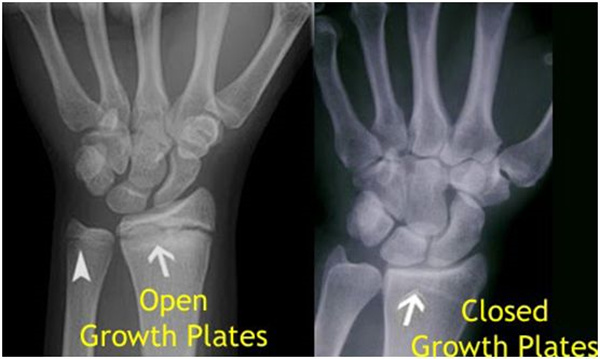

其實想要了解孩子的生長發(fā)育情況或者說孩子未來身高的趨勢,測骨齡是個好辦法。臨床上通常拍攝兒童的左手正位X光片 , 采用《中華-05》骨齡標(biāo)準(zhǔn)對手腕骨發(fā)育程度進行骨齡評價。

未成年時隨著年齡的增加骺軟骨端不斷骨化,骨骼就不斷增長。當(dāng)骨骺線完全閉合時骨骼就停止生長,個子也就不再增長了。一般骨骺端完全閉合的年齡是18~20歲左右。

一般來說,女孩的骨齡超過14歲,男孩的骨齡超過16歲,這時其骨骺線已接近閉合,基本沒有長高的機會了。

因此,越早了解骨骺線閉合情況,越早干預(yù),孩子長高的可能性越大。